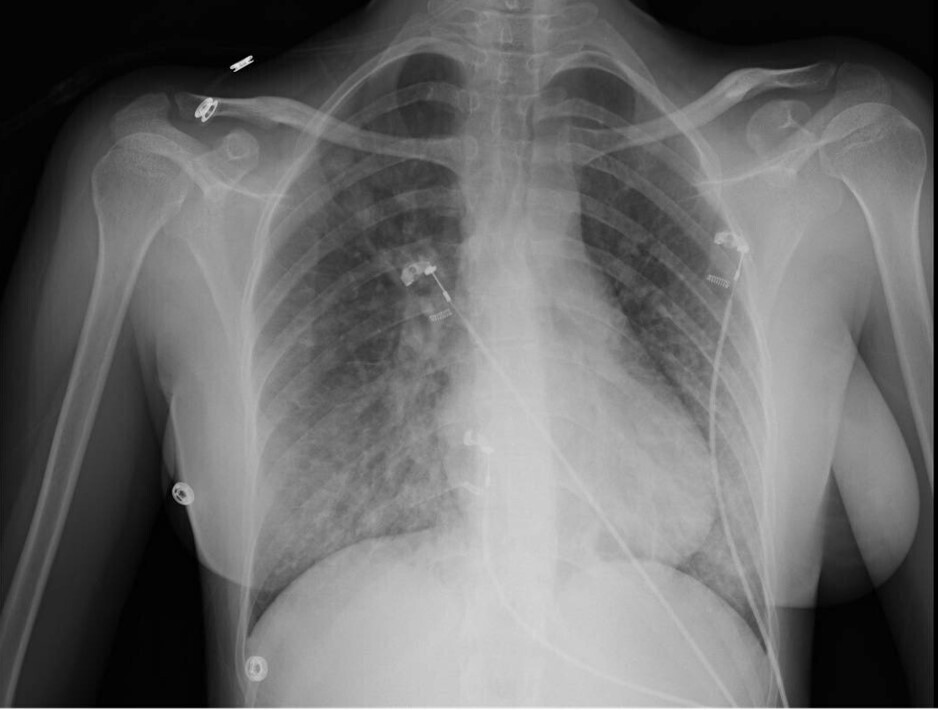

La radiographie thoracique est la suivante :

Question 8 : Cette radiographie thoracique montre…

Il s’agit d’une radiographie thoracique de face, en inspiration.

La silhouette cardio-médiastinale est normale, il n’y a pas de cardiomégalie.

Les culs-de-sac pleuraux sont libres, sans pneumothorax ni épanchement liquidien.

On constate la présence d’un syndrome alvéolo-interstitiel bilatéral, aux deux bases, avec une discrète prédominance à droite.

Pour résumer le tableau, il s’agit d’une patiente de 23 ans sans antécédents, hospitalisée pour une détresse respiratoire hypoxémiante, crépitante, subfébrile, associée à un syndrome alvéolo-interstitiel bibasal à la radiographie thoracique, avec une discrète prédominance à droite.